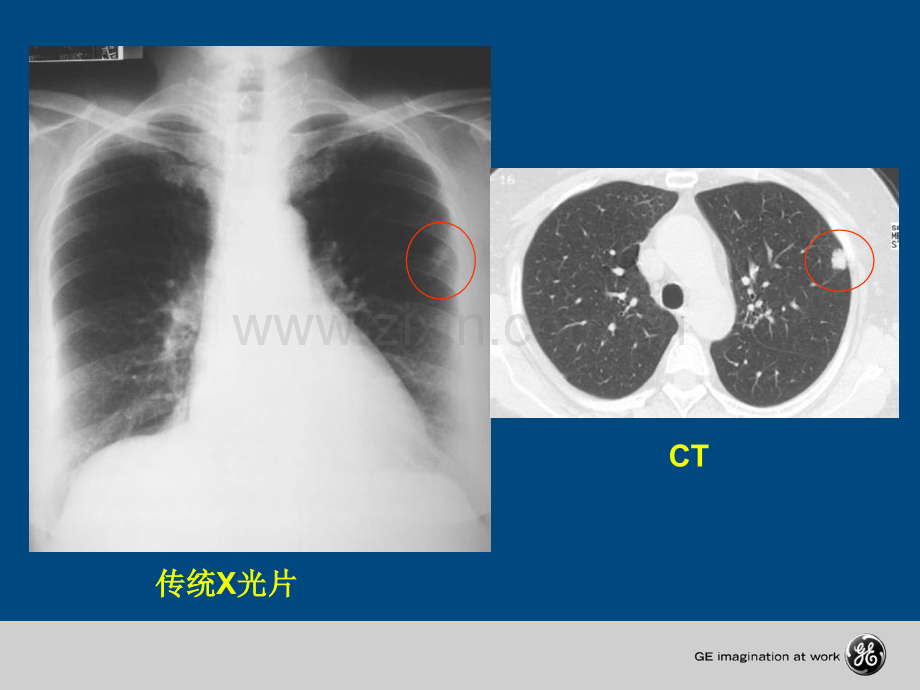

什么是什么是 CT?C Computerized计计 算算 机机 T Tomographe 断断 层层 扫扫 描描传统传统X光片光片CT 螺旋螺旋CT横断位扫描横断位扫描CT机的发展机的发展 CT 机机 房房 示示 意意 图图 CTCT机的基本组成机的基本组成机的基本组成机的基本组成X线球管线球管高压发生器高压发生器探测器和数据探测器和数据采集系统采集系统扫描床扫描床控制台控制台CT机的基本组成包括:机的基本组成包括:x线球管和高压发生器、探测器和数据线球管和高压发生器、探测器和数据采集系统、扫描架、扫描床及控制台采集系统、扫描架、扫描床及控制台 扫描架扫描架 球球 管管 发发 生生 器器 探探 测测 器器 高高 压压 发发 生生 器器 高高 电电 压压 球球 管管 人人 体体 D A S系统系统 计计 算算 机机 显显 示示 照照 相相 探探 测测 器器 X-rayCTCT的成像过程的成像过程的成像过程的成像过程CTCT机的基本组成机的基本组成机的基本组成机的基本组成X线球管线球管球管基本结构球管基本结构高速电子流轰击在阳极靶上产生高速电子流轰击在阳极靶上产生x射线射线冷却系统保证球管能连续高效的运转冷却系统保证球管能连续高效的运转球管球管 球管的评价指标球管的评价指标 1.1.球管焦点球管焦点 (mm x mm)mm x mm)2.2.阳极热容量阳极热容量 (MHu)MHu)3.3.阳极散热率阳极散热率(kHu/min)kHu/min)4.4.衡量球管能力的金标准:衡量球管能力的金标准:连续螺旋扫描时间(秒)连续螺旋扫描时间(秒)CTCT机的基本组成机的基本组成机的基本组成机的基本组成焦焦 点点 越越 小,小,图图 像像 越越 清清 晰晰 小焦点的成像小焦点的成像 大焦点的成像大焦点的成像 较较 大大 的的 模模 糊糊 区区 域域 图图 像像 清清 晰晰 球管的焦点球管的焦点CTCT机的基本组成机的基本组成机的基本组成机的基本组成 5 mm5 mmX-ray Tube Z axis扫描层厚扫描层厚2 x 5 mmCoverage/Rotation5 mm1 x 10 mm10 mm 多排螺旋多排螺旋CT覆盖范围覆盖范围/圈圈5 x 2 mm2 mmHigh ResLow ResCTCT机的基本组成机的基本组成机的基本组成机的基本组成传统的扫描架承载图像采集系统,可以前后倾斜;扫描床承载病人传统的扫描架承载图像采集系统,可以前后倾斜;扫描床承载病人扫描架扫描架扫描床扫描床CTCT机的基本组成机的基本组成机的基本组成机的基本组成进行扫描控制和图像显示及分析进行扫描控制和图像显示及分析控制台控制台CTCT机的基本组成机的基本组成机的基本组成机的基本组成通过控制台可与高级图像处理工作站和照相设备连接通过控制台可与高级图像处理工作站和照相设备连接控制台控制台CTCT机的基本组成机的基本组成机的基本组成机的基本组成 高高 压压 发发 生生 器器 高高 电电 压压 球球 管管 人人 体体 D A S 系统系统 计计 算算 机机 显显 示示 照照 相相 探探 测测 器器 X-rayCTCT的成像过程的成像过程的成像过程的成像过程CTCT扫描方式扫描方式扫描方式扫描方式 定位像扫描(定位像扫描(定位像扫描(定位像扫描(Scout scan)Scout scan)轴位扫描轴位扫描轴位扫描轴位扫描(Axial scan)Axial scan)螺旋扫描螺旋扫描螺旋扫描螺旋扫描(Helical scan)Helical scan)电影扫描电影扫描电影扫描电影扫描(Cine scan)Cine scan)球管位置固定,扫描床移动球管位置固定,扫描床移动定位像扫描定位像扫描CTCT扫描方式扫描方式扫描方式扫描方式扫描床位置固定,球管旋转曝光扫描床位置固定,球管旋转曝光轴位扫描轴位扫描CTCT扫描方式扫描方式扫描方式扫描方式球管旋转曝光,扫描床连续移动球管旋转曝光,扫描床连续移动螺旋扫描螺旋扫描CTCT扫描方式扫描方式扫描方式扫描方式Cine扫描床位置固定,球管持续曝光扫描床位置固定,球管持续曝光电影扫描电影扫描CTCT扫描方式扫描方式扫描方式扫描方式CTCT基本概念:基本概念:基本概念:基本概念:CTCT值值值值CT CT 值值值值:衡量组织密度的单位衡量组织密度的单位衡量组织密度的单位衡量组织密度的单位 CT CT CT CT 图图图图 像像像像 上上上上 每每每每 一一一一 个个个个 点点点点(像像像像 素素素素)的的的的 亮亮亮亮 度度度度 代代代代 表表表表 了了了了 该该该该 点点点点 所所所所 对对对对 应应应应 的的的的 人人人人 体体体体 组组组组 织织织织 对对对对 X-RAY X-RAY X-RAY X-RAY 的的的的 吸吸吸吸 收收收收 程程程程 度度度度,它间接反应了该点组织的密它间接反应了该点组织的密它间接反应了该点组织的密它间接反应了该点组织的密 度,为度,为度,为度,为 了了了了 定定定定 量量量量 地地地地 反反反反 映映映映 不不不不 同同同同 组组组组 织织织织 间间间间 的的的的 密密密密 度度度度 差差差差 异异异异,人人人人 们们们们 规规规规 定定定定:将将将将 水水水水 的的的的 密密密密 度度度度 值值值值 定定定定 为为为为 0,0,0,0,将将将将 气气气气 体体体体 的的的的 密密密密 度度度度 值值值值 定定定定 为为为为-1000,-1000,-1000,-1000,其其其其 它它它它 组组组组 织织织织 的的的的 密密密密 度度度度 值值值值 与与与与 上上上上 述述述述 标标标标 准准准准 对对对对 照照照照 求求求求 得得得得,它它它它 的的的的 单单单单 位位位位 为为为为 HuHuHuHu。CT CT CT CT 值值值值 会受到设备精度、操作方法、伪影等因素的会受到设备精度、操作方法、伪影等因素的会受到设备精度、操作方法、伪影等因素的会受到设备精度、操作方法、伪影等因素的干扰。干扰。干扰。干扰。谢谢 谢!谢!